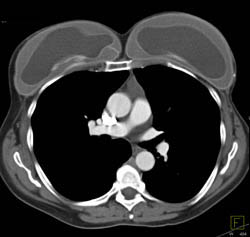

Ductus Aneurysm